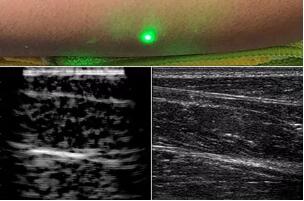

目前,研究人員已經(jīng)與健康的志愿者測試了他們的系統(tǒng):從半米遠(yuǎn)處掃描了他們的前臂,并將這些結(jié)果與傳統(tǒng)超聲的結(jié)果進(jìn)行了比較。他們能夠觀察到深達(dá)6厘米的組織,并能看到肌肉,脂肪和骨頭,并報(bào)告其結(jié)果可與標(biāo)準(zhǔn)超聲相媲美。

研究人員用一種激光裝置測試了這個想法,該裝置使用一個波長為1,550納米的脈沖激光來產(chǎn)生聲波,并使用第二個連續(xù)激光,調(diào)諧到相同的波長以遠(yuǎn)程檢測反射的聲波。第二個激光器是靈敏的運(yùn)動檢測器,可測量聲波從肌肉,脂肪和其他組織反射回來而引起的皮膚表面振動。反射的聲波產(chǎn)生的皮膚表面運(yùn)動會導(dǎo)致激光頻率發(fā)生變化,這種變化可以測量。通過機(jī)械掃描人體上的激光,科學(xué)家可以獲取不同位置的數(shù)據(jù)并生成該區(qū)域的圖像。